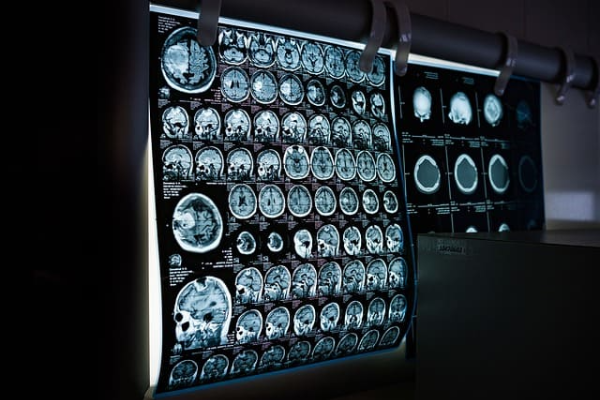

✅ CT 검사란?

CT(Computerized Tomography)는 X-ray를 다양한 각도에서 인체에 투과시켜 단면 영상을 생성하는 검사입니다.

단순 엑스레이보다 훨씬 정밀하며, 장기, 뼈, 혈관의 3차원 형태를 빠르게 확인할 수 있어 응급 상황 진단에 특히 유용합니다.

🩺 CT 주요 활용 예

- 두부 외상, 뇌출혈 여부 확인

- 폐질환 (폐렴, 결절, 폐암) 진단

- 간·담낭·췌장 질환 확인

- 신장 결석, 복부통증 원인 파악